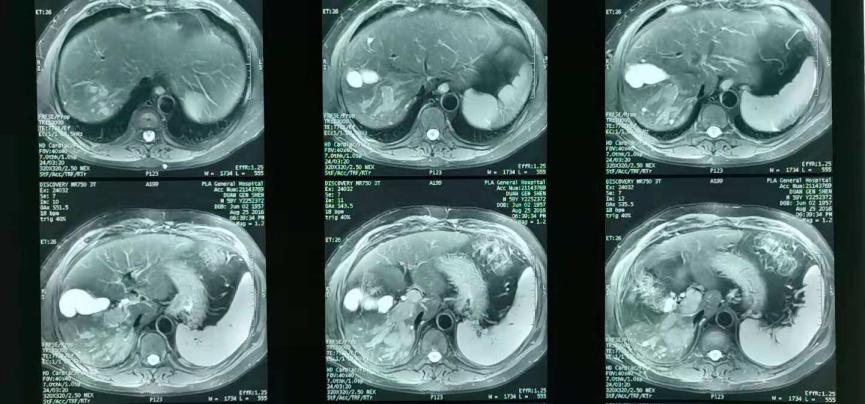

2017年4月15日复查,疾病进展(图3)。出现门腔静脉间淋巴结转移(图4)。

图3.术后7个月复查腹部MR

图4.术后7个月复查腹部MR 门腔静脉间淋巴结转移